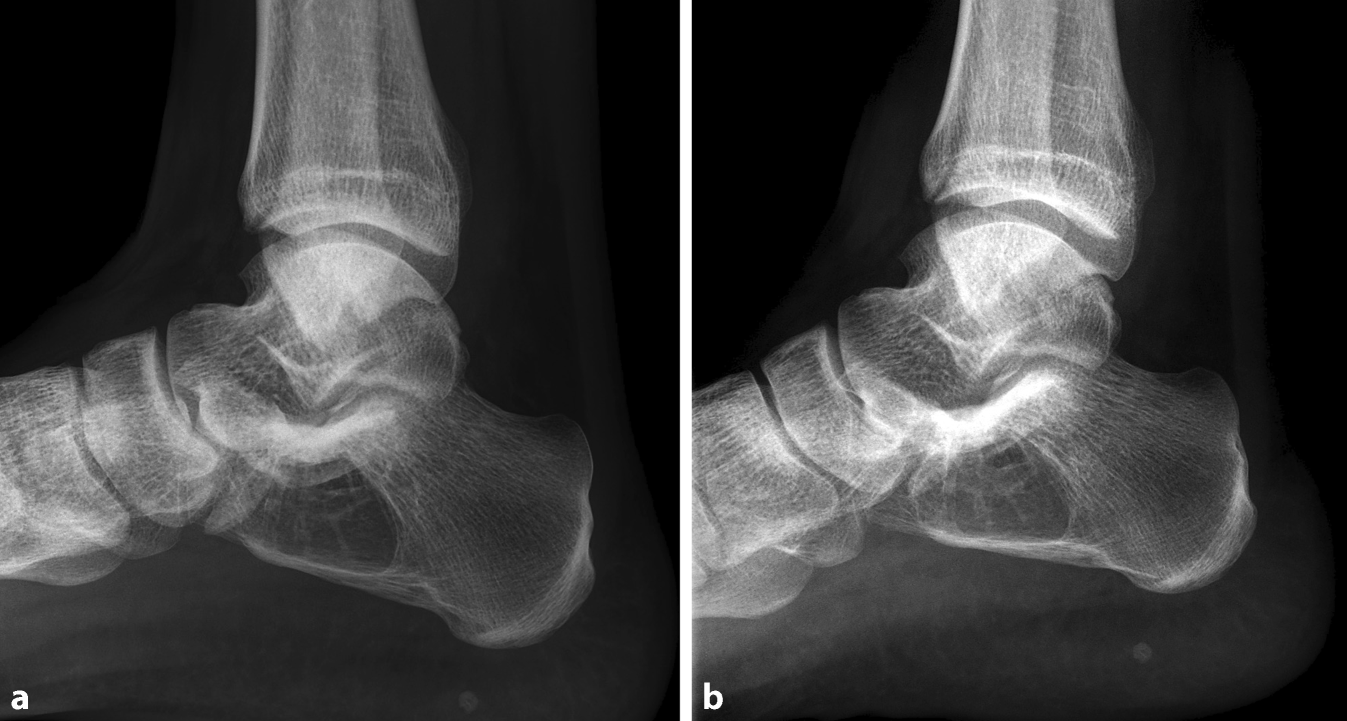

Ein 36-jähriger Patient klagte über seit längerer Zeit bestehende, stechende Schmerzen am rechten Sprunggelenk bzw. Fuß ohne vorangegangenes Trauma. Die klinische Untersuchung erbrachte bis auf Senk‑/Spreizfüße beidseits und einen leichten Druckschmerz über der Ferse plantar keine weiteren Auffälligkeiten. Im Röntgenbild des rechten Sprunggelenks war eine gut randsklerosierte, ventral im Kalkaneus gelegene, radioluzente Läsion nachweisbar.

Die typische Lage und das radiologische Erscheinungsbild führte zur Verdachtsdiagnose eines intraossären Kalkaneuslipoms (siehe unten; Abb. 4a). Die Beschwerden wurden auf die Fußfehlstellung selbst zurückgeführt. Daher wurde keine bildgebende Verlaufskontrolle oder weitere Therapie für das Kalkaneuslipom empfohlen. Aufgrund der Beschwerden am Fuß selbst wurde nach 7 Monaten erneut eine Röntgendiagnostik durchgeführt, in der sich das Kalkaneuslipom völlig unverändert zeigte (Abb. 4b).

Abb. 4

Röntgenbild der rechten Ferse (seitlich) eines 36-jährigen Patienten mit unspezifischen Schmerzen am rechten Fuß. Ventral im Kalkaneus ist das radioluzent imponierende, deutlich randsklerosierte Kalkaneuslipom nachweisbar (a), das im mittelfristigen Verlauf (7 Monate) völlig unverändert erscheint (b)

Fachlicher Hintergrund – Kalkaneuslipom

Das Kalkaneuslipom stellt einen klassischen Zufallsbefund eines benignen Knochentumors im Röntgenbild dar, der bei Abklärung von Fußbeschwerden anderer Ursache oder in Folge eines Unfalls entdeckt wird. Das Kalkaneuslipom präsentiert sich im Röntgenbild als deutlich randsklerosierte, radioluzente Läsion (Abb. 4; [17]). In der MRT weist sie – da aus Fettgewebe bestehend – eine hyperintense Signalbildgebung in der T1-Wichtung auf, umgeben von einem hypointensen Randsaum (d. h. die Sklerosezone; [18]).